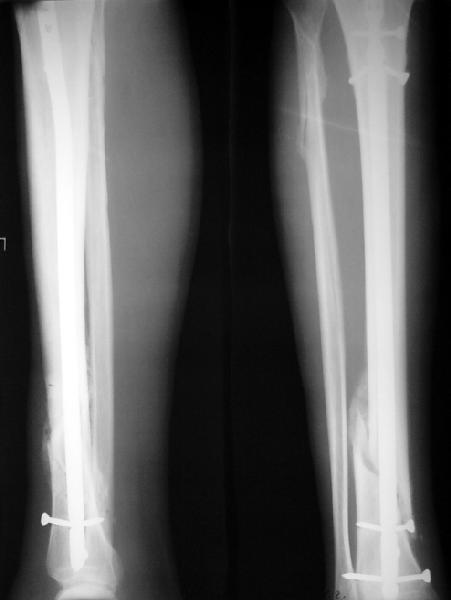

На мой взгляд, на снимках, приведённых Вами - неправильно сростающийся перелом дистальной трети большеберцовой кости, состояние после остеосинтеза интрамедуллярным гвоздём.

Как Вы пишите снимок под номером 1 - менсяц после операции, под номером 2- два месяца после операции.

Вы не послали послеоперационный снимок, поэтому трудно судить о состоянии редукции после операции.

Позвольте по поводу техники операции высказать своё мнение...

Установка с медиальной стороны гвоздя в области дистального фрагмента дополнительного шурупа помогло бы Вам репонировать и удержать перелом в анатомическом положении, предотвратило варусную деформацию и смещение по ширине.

Кстати, если можно пошлите послеоперационный снимок.

На мой взгляд внутрикостная фиксация переломов дистальной и проксимальной трети большеберцовой кости, за исключением поперечных, не очень хорошее решение вопроса, аппарат Илизарова или Тэйлора, позволяющие призвести закрытую анатомическую редукцию и отличное удержание отломков в период сращения.

Пример, приведённый Вами в нашей дискуссии по времени нагрузки после остеосинтеза не совсем удачный... Ваш больной имеет счастье, что первым согнулся проксимальный замыкающий винт, а не дистальный и гвоздь не пенетрировал голеностопный сустав.